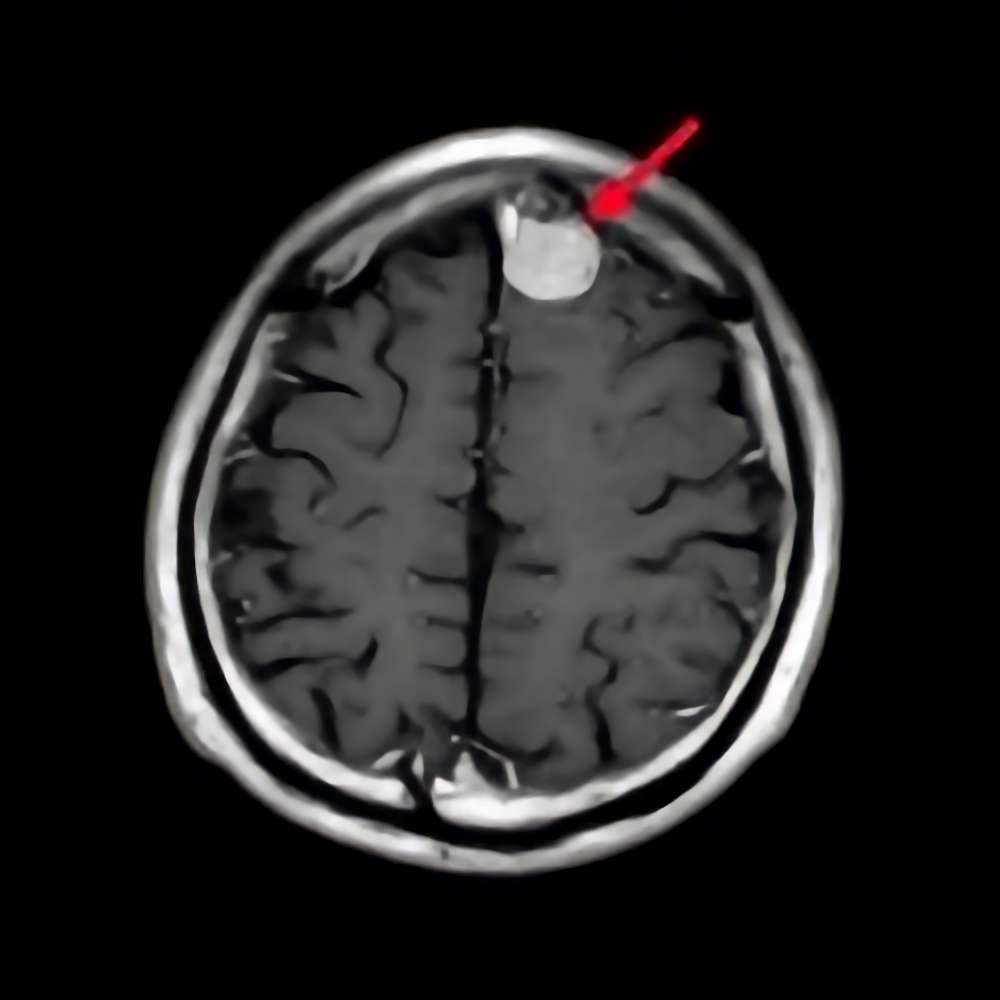

断層撮影

手術前1

手術前2